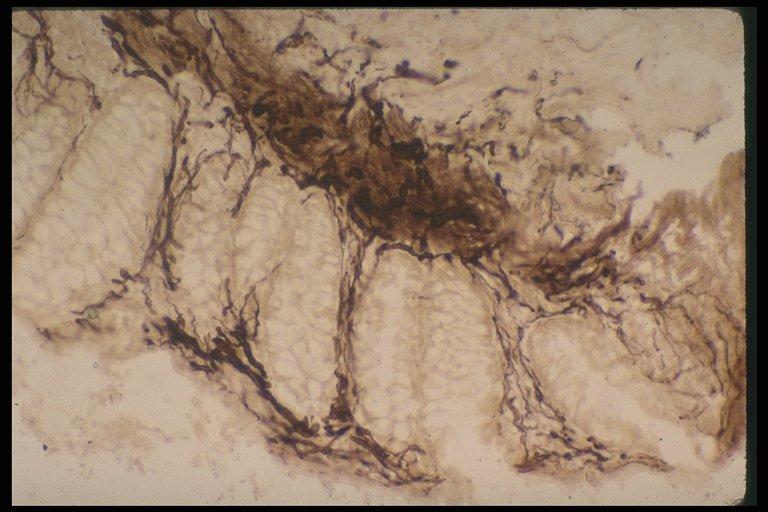

Increased acetylcholinesterase activity in Hirschsprung's disease, thick staining is observed in mucosa and submucosa layer